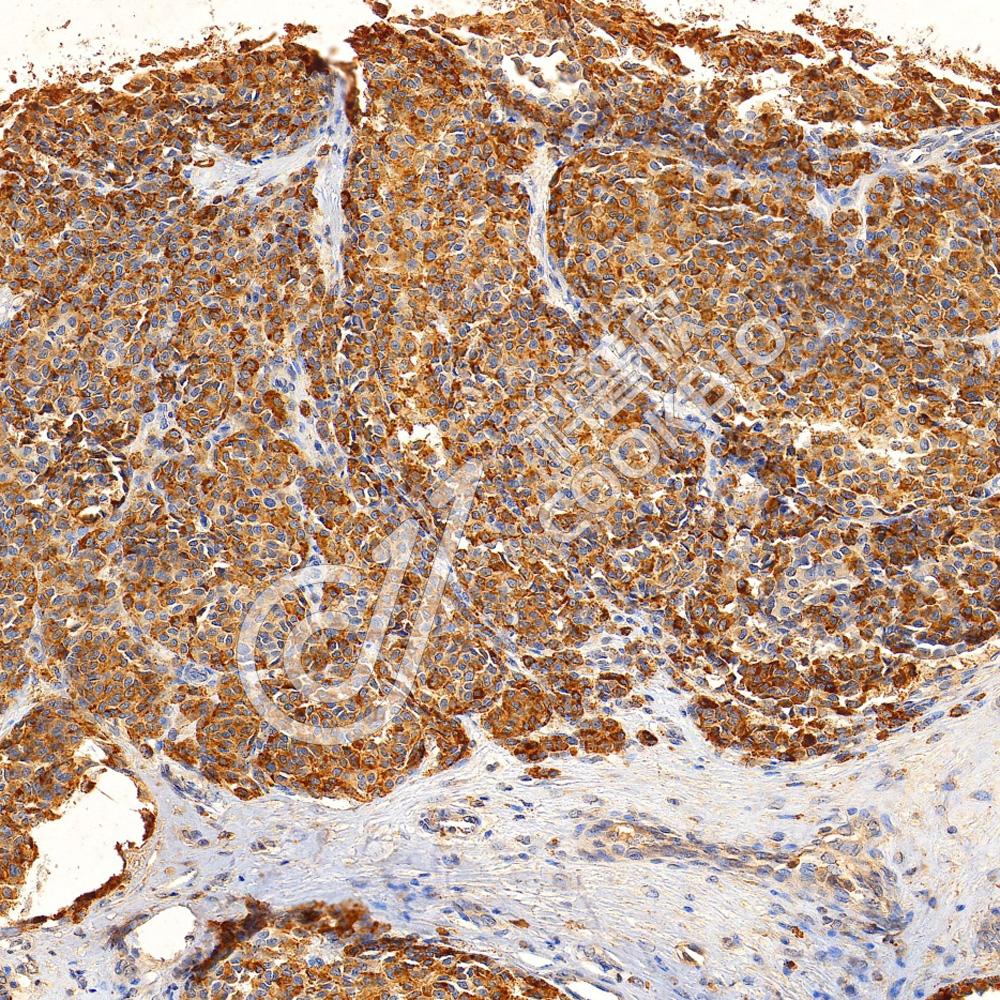

IHC检测Melanoma gp100蛋白(货号 K5450480).

样品: 人黑色素瘤, 4%多聚甲醛 (货号KSG1101) 固定12-24小时.

抗原修复: Tris-EDTA抗原修复液(pH 9.0) (货号KSG1203), 水浴100℃, 25分钟.

—抗: 1: 1000稀释, 4℃ 孵育过夜.

二抗: S-vision免疫组化多聚二抗(山羊抗小鼠), 即用型(货号KB3903), 室温孵育20分钟.